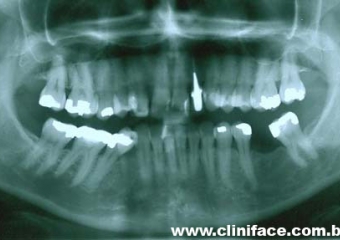

Raio X mostrando agenesia do elemento 12, reabilitado com implante e prótese fixa em porcelana